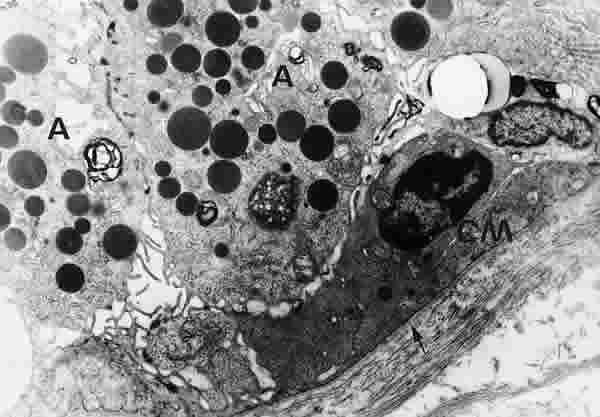

Figura 31

BIOPSIA EN UNA PERSONA CONTROL. EN EL POLO BASAL DE LAS CÉLULAS ACINARES (A) EXISTE GRAN CANTIDAD DE GRÁNULOS DE SECRECIÓN Y ABUNDANTES ORGÁNULOS SUBCELULARES. SE OBSERVA UNA CÉLULAS MIOEPITELIAL (CM). LA MEMBRANA BASAL (FLECHA ARRIBA) ES ANCHA Y CONTINUA. MICROSCOPIA ELECTRÓNICA. MAGNIFICACIÓN ORIGINAL X5000.